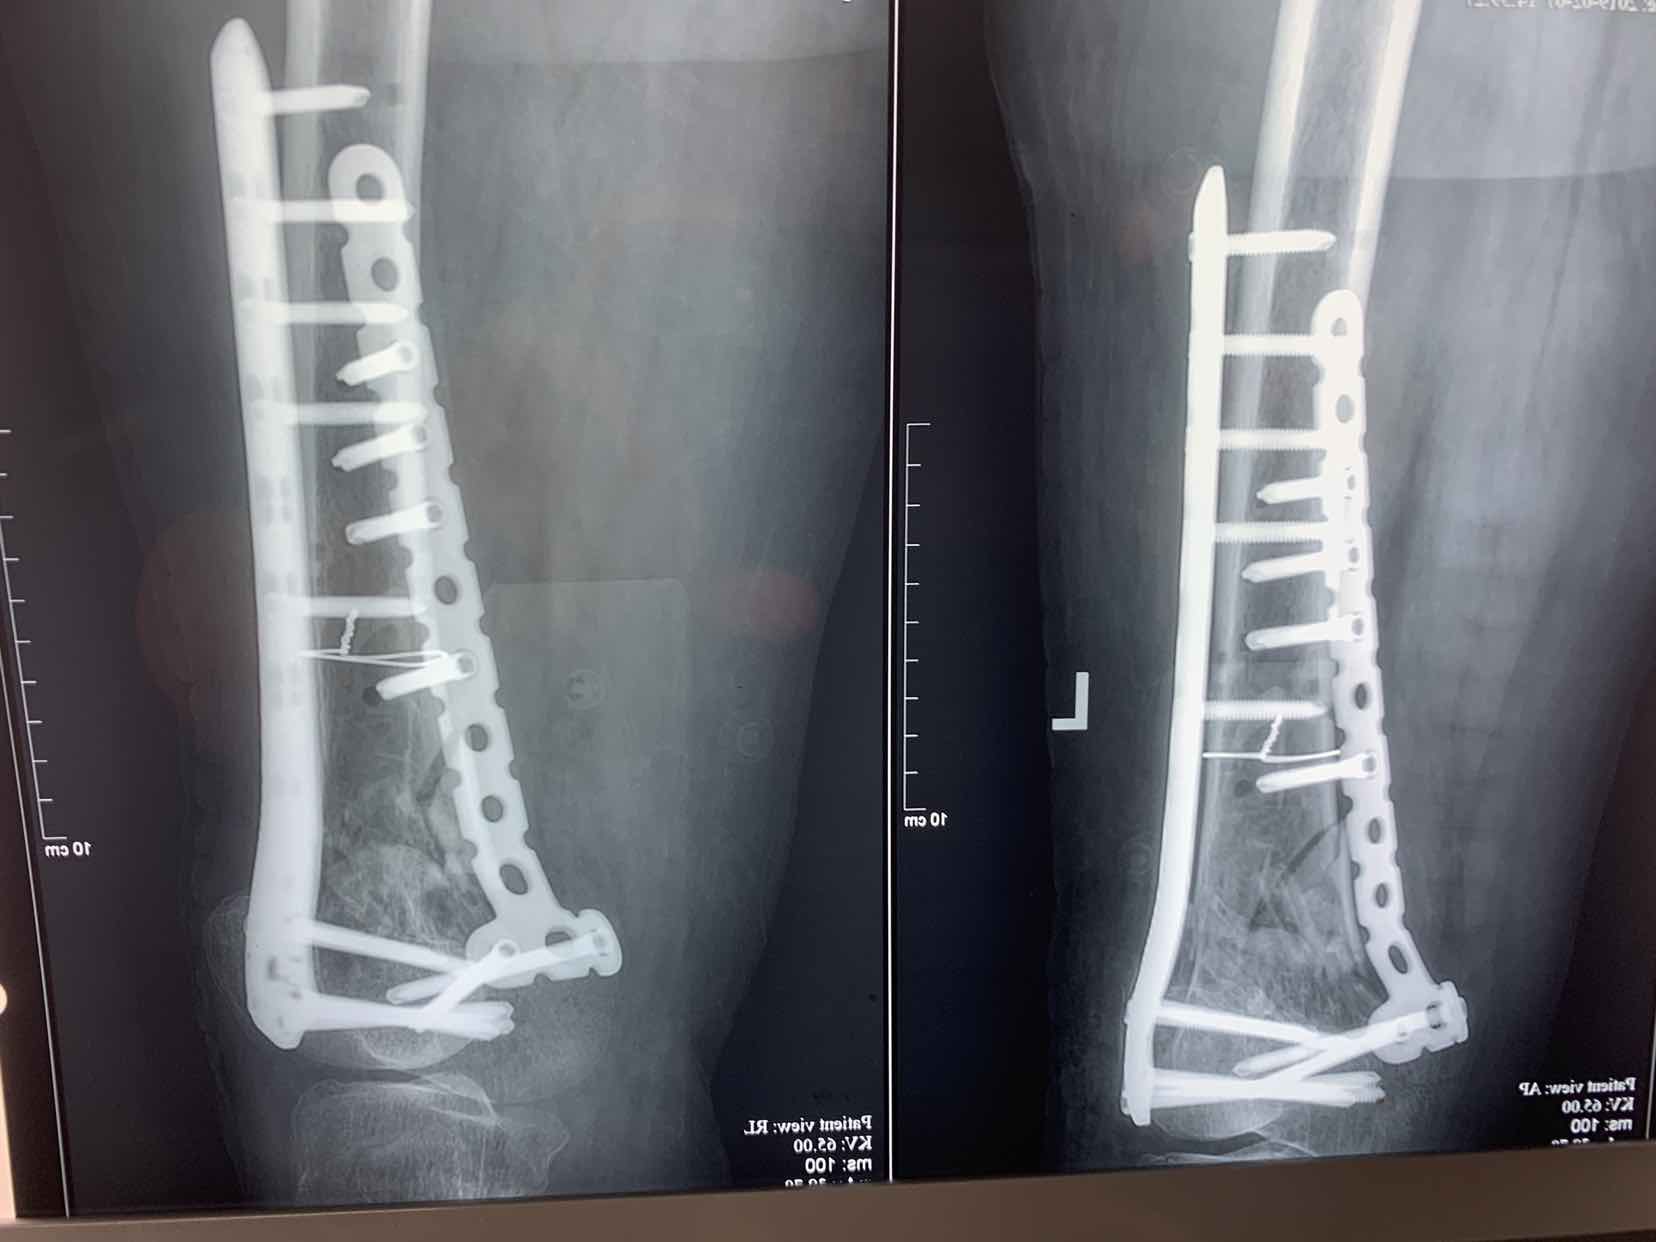

诊断左侧股骨髁上粉碎性骨折。硬膜外麻醉下行切开复位内固定术,术中局部复位,患者长期卧床,骨皮质较脆,超薄。可见局部骨质缺损,术中植入人工骨,填充髓腔。双侧锁定钢板内固定。术后常规抗炎,接骨药,抗凝药物治疗。患者后期出现贫血低蛋白血症,予以纠正。

对于老年人股骨髁上粉碎性骨折临床多见,这类患者大多局部骨质较差,不容易愈合,骨缺损还是建议术中植骨,术后持续接骨药治疗,并积极控制血栓,贫血,低蛋白血症等并发症。